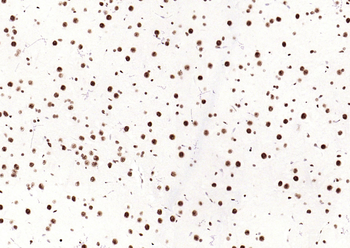

100 μl, 200 μl, 50 μlSMAD7 Rabbit Polyclonal Antibody [orb500819]

FC, ICC, IF, IHC-Fr, IHC-P, WB

Bovine, Porcine

Human, Mouse, Rat

Rabbit

Polyclonal

Unconjugated

100 μl, 200 μl, 50 μlPhospho-Smad3 (Ser213) Rabbit Polyclonal Antibody [orb106193]